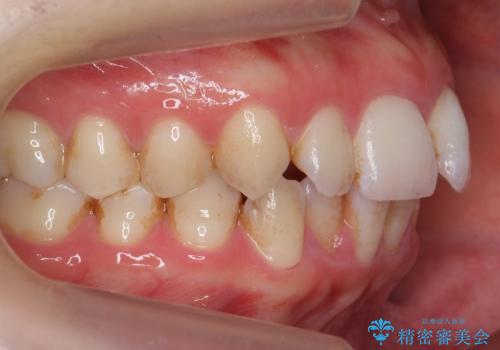

- 表面の着色を気にされて、ご来院されました。

お話しをしたところ、リーズナブルに短時間で綺麗にしたいとの事でした。

そこでPMTCの30分コースで、目立つ部分を中心に落としていきました。